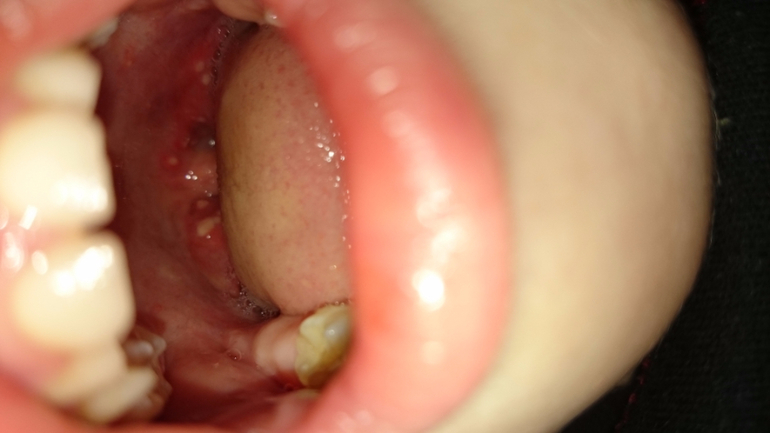

Вирусные инфекцииПоследний диагноз был ангина фолликулярная,до этого ставили ротовирус,сегодня появилась сыпь .Начну с начала....В четверг после тихого часа мне позвонила воспитатель с детского сада и сказала забрать дочь,так как у нее острый коньюктевит. У ребенка один глаз почти не открывался,начали лечить...на следующий день второй глазик стал таким же...к вечеру ребенок истерил и жалоба была уже на животик.Уложили спать.Через час ее во сне обильно вырвало,еще через час поднялась высокая температура под 40 с которой мы два дня боролись каждые 3 часа,через день я заметила на горле белые гнойнички,сказала врачу на что вразумительного ответа не последовало,после я вызвала скорую,которая диагноз тоже не поставила а лишь предложила лечь в больницу,мы отказались,приехала детская неотложка, которая поставила фолликулярная ангину, выписали нам антибиотики,сегодня температура выше 38 не поднималась,но появилась не понятная сыпь,которая очень чешется. Так что же это за бяка такая?кто сталкивался с подобным?